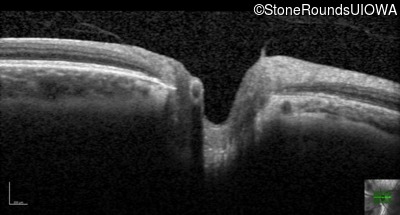

Age at visit: 41 years (Visit 2)

OD OS

This 41 year old woman was highly myopic as a child and experienced a rhegmatogenous retinal detachment OS at age 20.

Refraction OD:     -17.25 +1.00 x 93

Refraction OS:     -18.25 +3.50 x 56

The clinical features favoring the diagnosis of Sticker syndrome in this patient include extensive radial lattice degeneration, a personal and family history of rhegmatogenous retinal detachment, a history of cataract surgery before age 30 (and very high myopia before that), arthritis in her knees and hips and a slightly flattened mid-face.